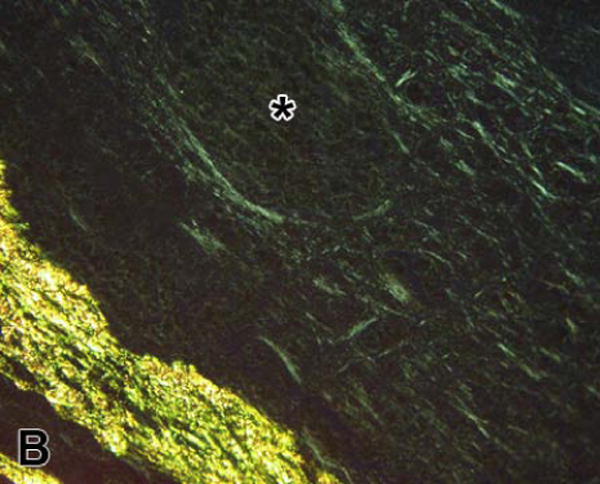

Fibrin stained with picrosirius red appeared yellow when observed with brightfield illumination, but pale green when viewed with polarized light (Figure 1). In contrast, although the other main component of the thrombus, red blood cells, also appeared yellow in brightfield, the cells were not birefringent and so could not be seen with polarized light (although not present in this thrombus, platelets also stain yellow, but are non-birefringent). Thus, the combination of picrosirius red staining and polarized light microscopy provided a method of identifying fibrin and differentiating it from other blood elements. In addition, the fibrous nature and organization of fibrin can be qualitatively appreciated when viewed with polarized light.

Figure 1.

Arterial thrombus stained with picrosirius red; (A) viewed with brightfield illumination; fibrin and red blood cells stain yellow while collagen stains red, (B) the same field viewed with linearly polarized light; fibrin appears pale green, red blood cells appear dark, and collagen fibers are much brighter than the fibrin fiber bundles and appear green, yellow, or orange (the color changes as fiber thickness increases). The region marked with the asterisk contains mainly red blood cells; however, the polarized image shows some thin fibrin fiber bundles present there also. [bar = 50 μm]